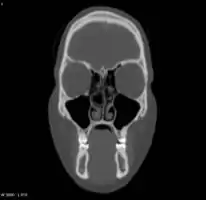

Right concha bullosa with air fluid level within